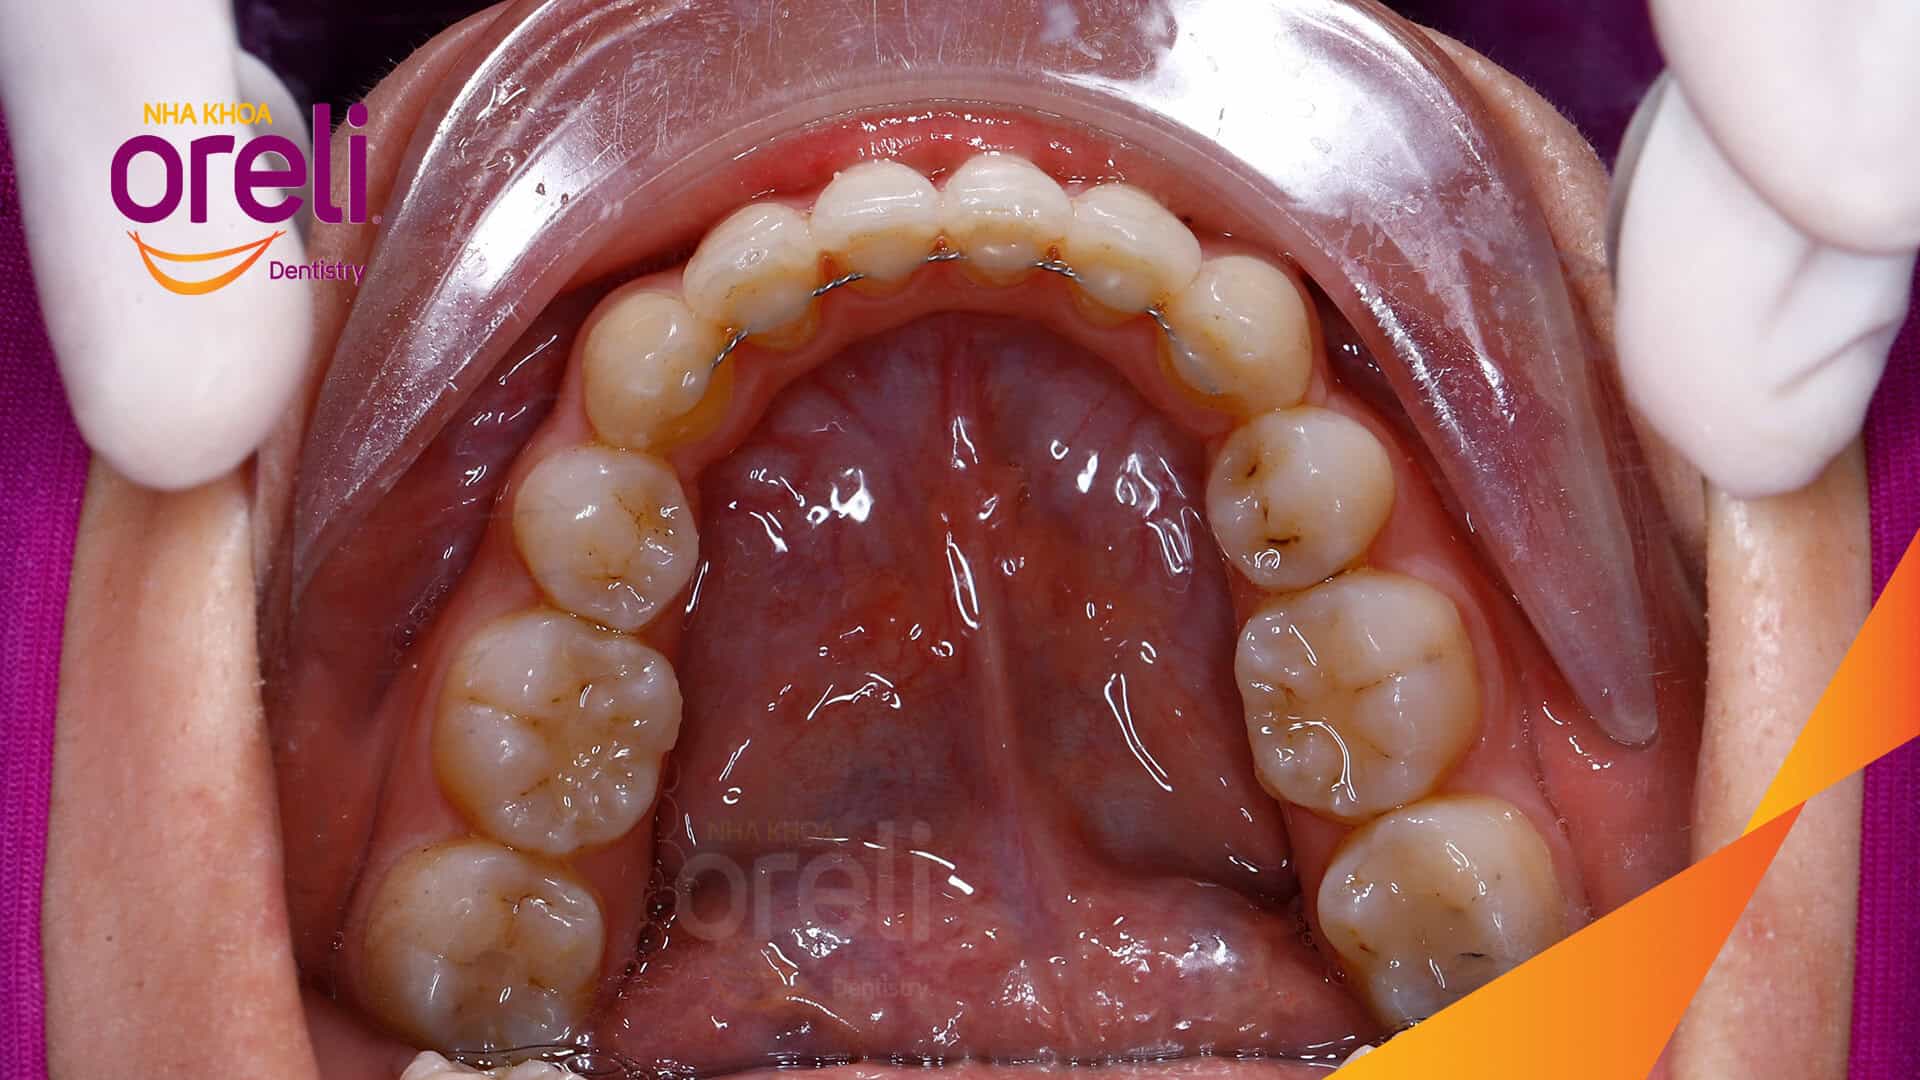

Tình trạng: Răng hô nhô xương ổ hai hàm

Giải pháp: Nhổ 4 răng số 4 niềng răng với măc cài kim loại

Dưới đây là một ca nắn chỉnh niềng răng hô có nhổ răng số 4 tại Oreli.